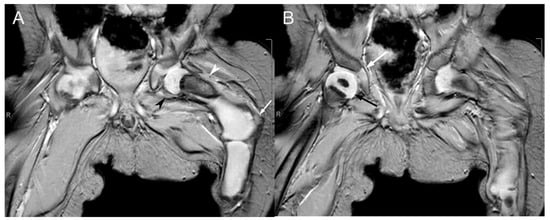

2.1. Case 1

2.2. Case 2